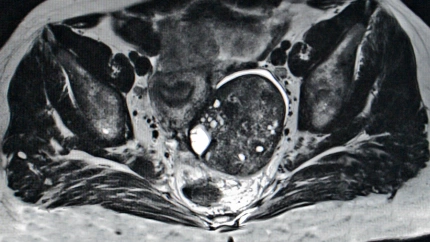

Imagen de recurso

¿Esto por qué ocurre? ¿Por qué la combinación de ambos fármacos podrían mejorar la supervivencia en estas pacientes? Según el doctor González, es posible que estas estatinas "ayuden a revertir algunos de los mecanismos de resistencia a inhibidores de PARP, como niraparib".

Los inhibidores de PARP son fármacos que se usan para tratar a algunas mujers con cáncer avanzado de ovario que ha regresado después de un tratamiento previo, según recoge el National Cancer Institute.

Estamos, en cualquier caso, ante unos resultados previos y todavía falta mucha información, pero esto podría ser, desde luego, el germen de algo revolucionario. De hecho, todavía no se conocen datos sobre si la toma de estatinas en pacientes de cáncer, sin problemas de colesterol, podría tener efectos negativos sobre su metabolismo.

En cualquier caso, el doctor apunta que tampoco hay información sobre si este descubrimiento "será aplicable a todas las pacientes", pero lo que sí es evidente que se ha abierto una línea de investigación sobre este hallazgo.